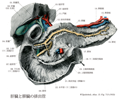

十二指腸Duodenum(Duodenum)

十二指腸【じゅうにしちょう】 The ca. 25-30 cm long segment of the small intestine between the pylorus and duodenojejunal flexure.(十二指腸は胃の幽門から十二指腸空腸曲まで約25cmの腸管。十二指腸Duodenumは12で、intestinum duodenum digitorumの意味。長さが指を12本横にならべた幅に等しいことによる。第1腰椎の椎体右縁の前方ではじまり、C字状に屈曲して膵臓の頭を取り囲む。腸間膜を欠き、後腹膜臓器の一つであり、胆管、膵管が開口するなど他の小腸とは異なる。十二指腸には4部が区別される。上部は幽門につづく5cmの長さの部で、上背外側へはしる。最初の2.5cmは可動性。上縁には小綱が付着する。上十二指腸曲において、ほぼ下方へ屈曲し、下行部(約8cm)へ移行する。その半ばで後内側壁に一条の十二指腸ヒダがり、その下端に大十二指腸乳頭が隆起し、ここに総胆管と膵管が共通に開口する。その上方2~3cmの部に小十二指腸乳頭があることが多く、副膵管の開口をみる。下行部は下十二指腸曲で左方へ屈曲し、水平部(下部、約8cm)へ移行し、第3腰椎体左縁に達し、左上方へ屈曲し、上行部へつづく。この部は約5cm走行したのち、第2腰椎の左方で急に前方に曲がり空腸へ移行する。この部を十二指腸空腸曲という。この曲がりは、横隔膜直下の後大動脈壁から下降する十二指腸提筋で固定されている。十二指腸の前半、ほぼ大小十二指腸乳頭までには、よく発達した十二指腸腺がある。複合管状胞状腺で、分泌物は粘液性でアルカリ性を示すことから胃酸から粘膜を保護するのではないかといわれる。)